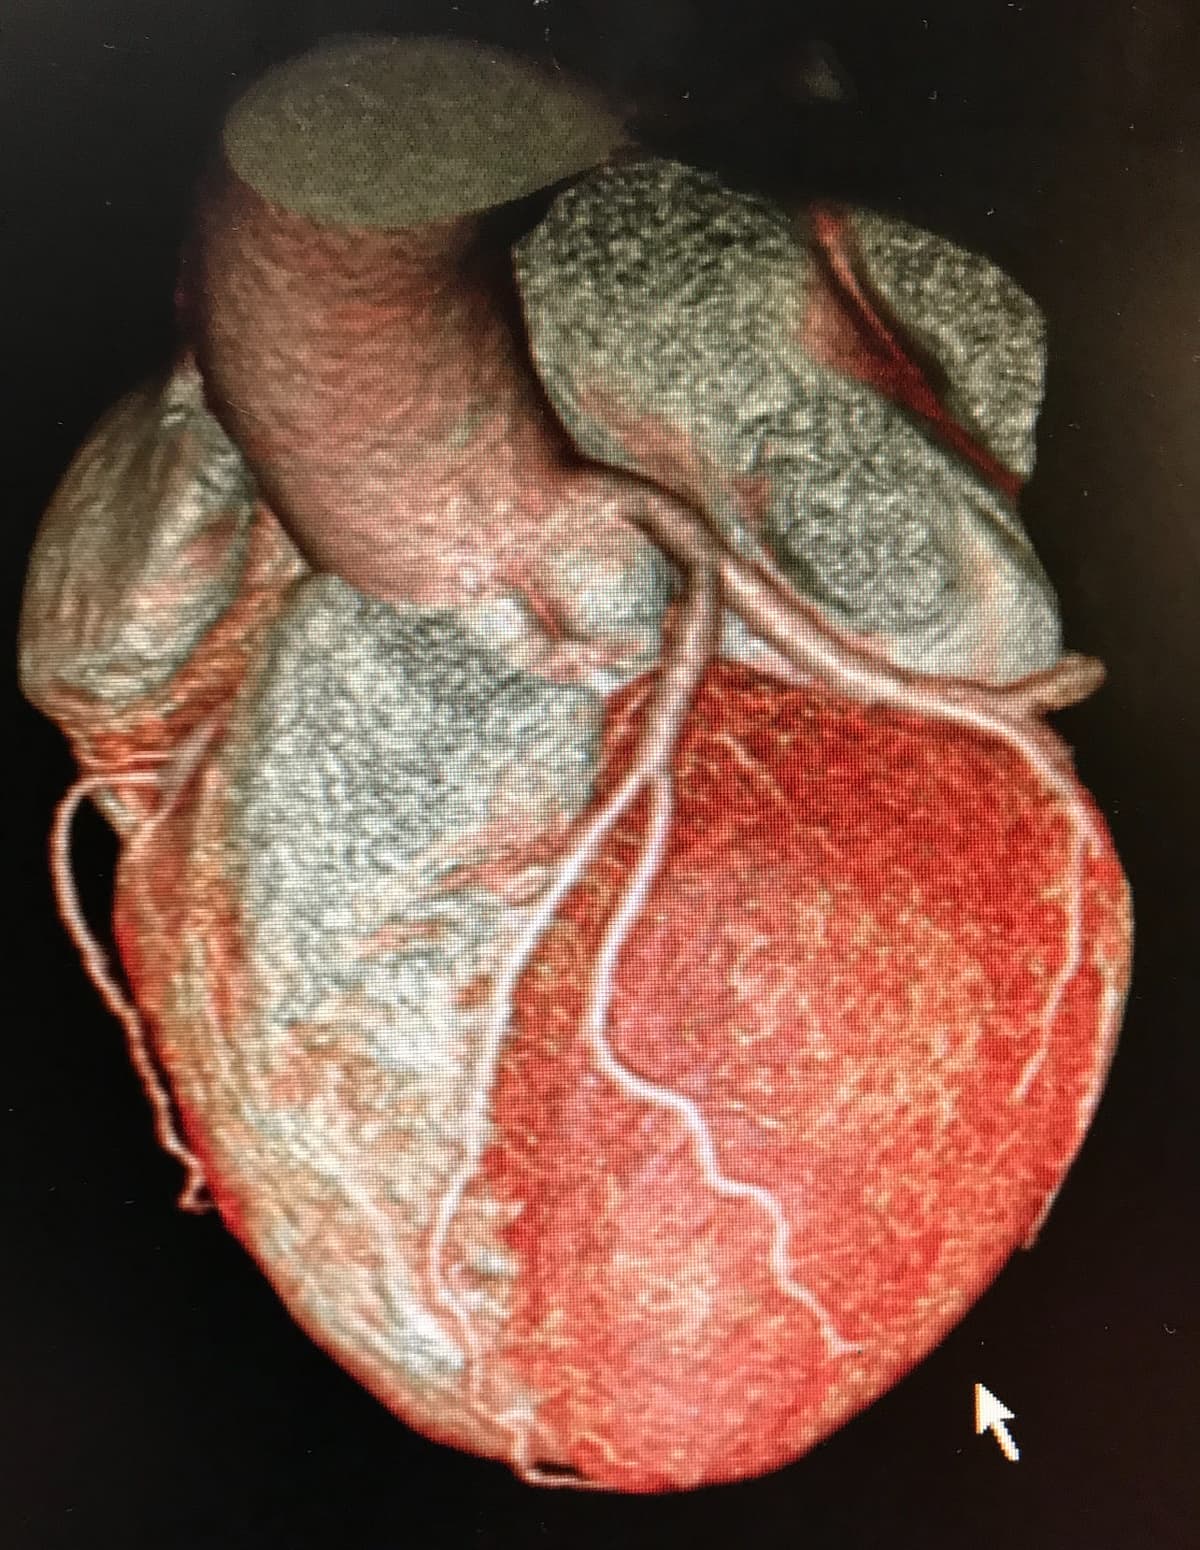

- CT / Coronary Calcium Score